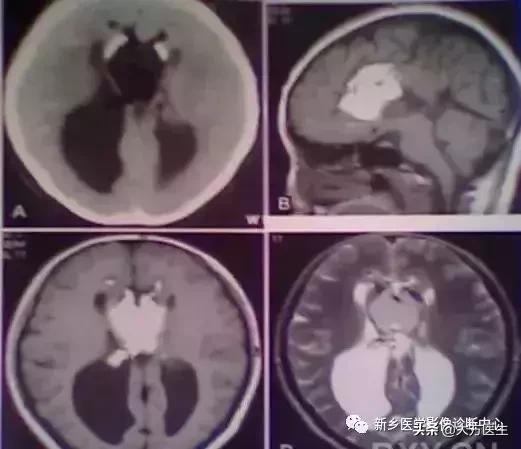

3、颅咽管瘤

多见于20岁以下,常有内分泌代谢障碍及视觉障碍,部分可有颅高压表现。

X:可见鞍区钙化,蝶鞍异常扩大及颅高压征象。CT:见囊实性肿块,囊壁斑块、蛋壳样钙化。MR:T1高等低混杂信号,T2为高信号。